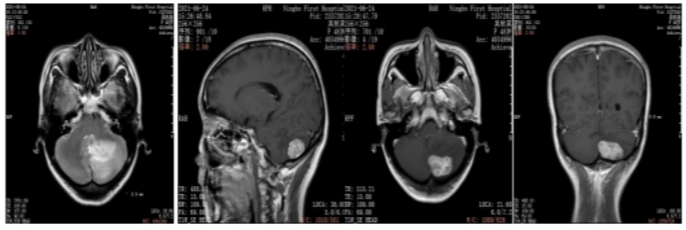

2022年5月颅脑增强MRI:左侧小脑肿瘤切除术后改变。

疗效评价CR,继续维持曲妥珠单抗(汉曲优)+吡咯替尼+卡培他滨治疗方案

图3.颅脑增强MRI